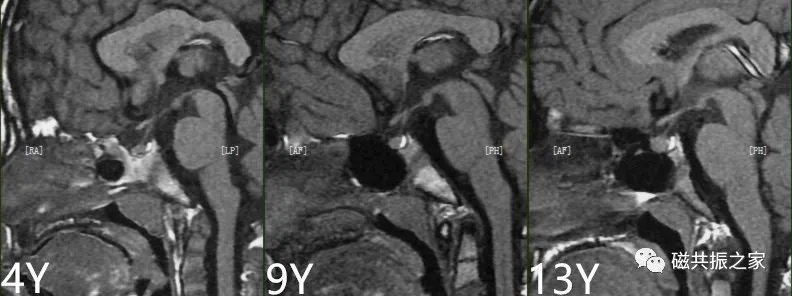

垂体高度与年龄相关,一般不会超过10mm。婴儿、儿童不大于6mm,成年男性及绝经后妇女不大于8mm,育龄期妇女为10mm,妊娠晚期及产后妇女可为12mm。当然成年人垂体的高度也不能过低,如小于5mm,就应引起重视,考虑是否存在异常。

在不同的年龄阶段,垂体的MRI信号有所不同,新生儿整个垂体在T1WI上表现为高信号,约6周以后,垂体前叶的信号强度逐渐减弱并最终与脑皮质相似,而垂体后叶组织内具有较多的神经分泌囊泡则表现为高信号,若高信号缺失则可能与中枢性尿崩症或垂体腺瘤受压有关。

腺垂体可以分泌多种激素,其在T1WI上呈相对低信号,与脑皮质信号相仿;神经垂体虽然不分泌激素,但其可储存下丘脑分泌的激素,在T1WI上常表现为高信号。